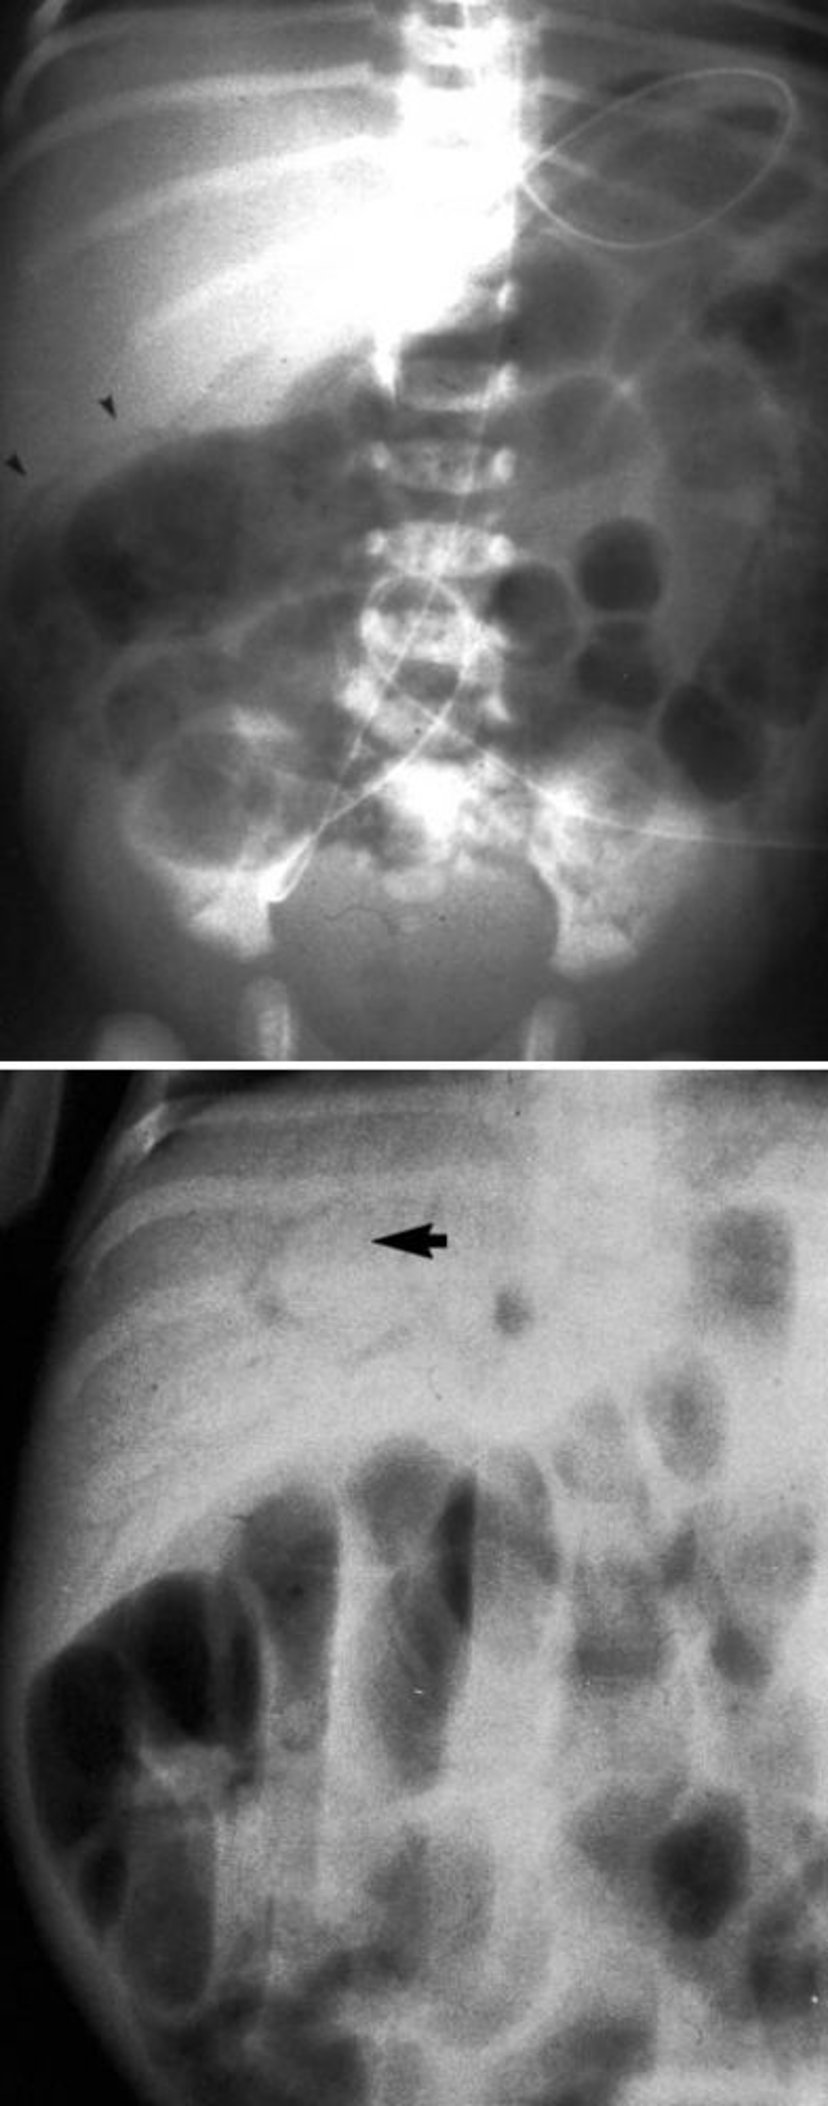

Esta imagen muestra neumatosis intestinal (superior, puntas de flecha) y gas en la vena porta (inferior, flecha).

By permission of the publisher. From Langer J: Gastroenterology and Hepatology: Pediatric Gastrointestinal Problems. Edited by M Feldman (series editor) and PE Hyman. Philadelphia, Current Medicine, 1997.